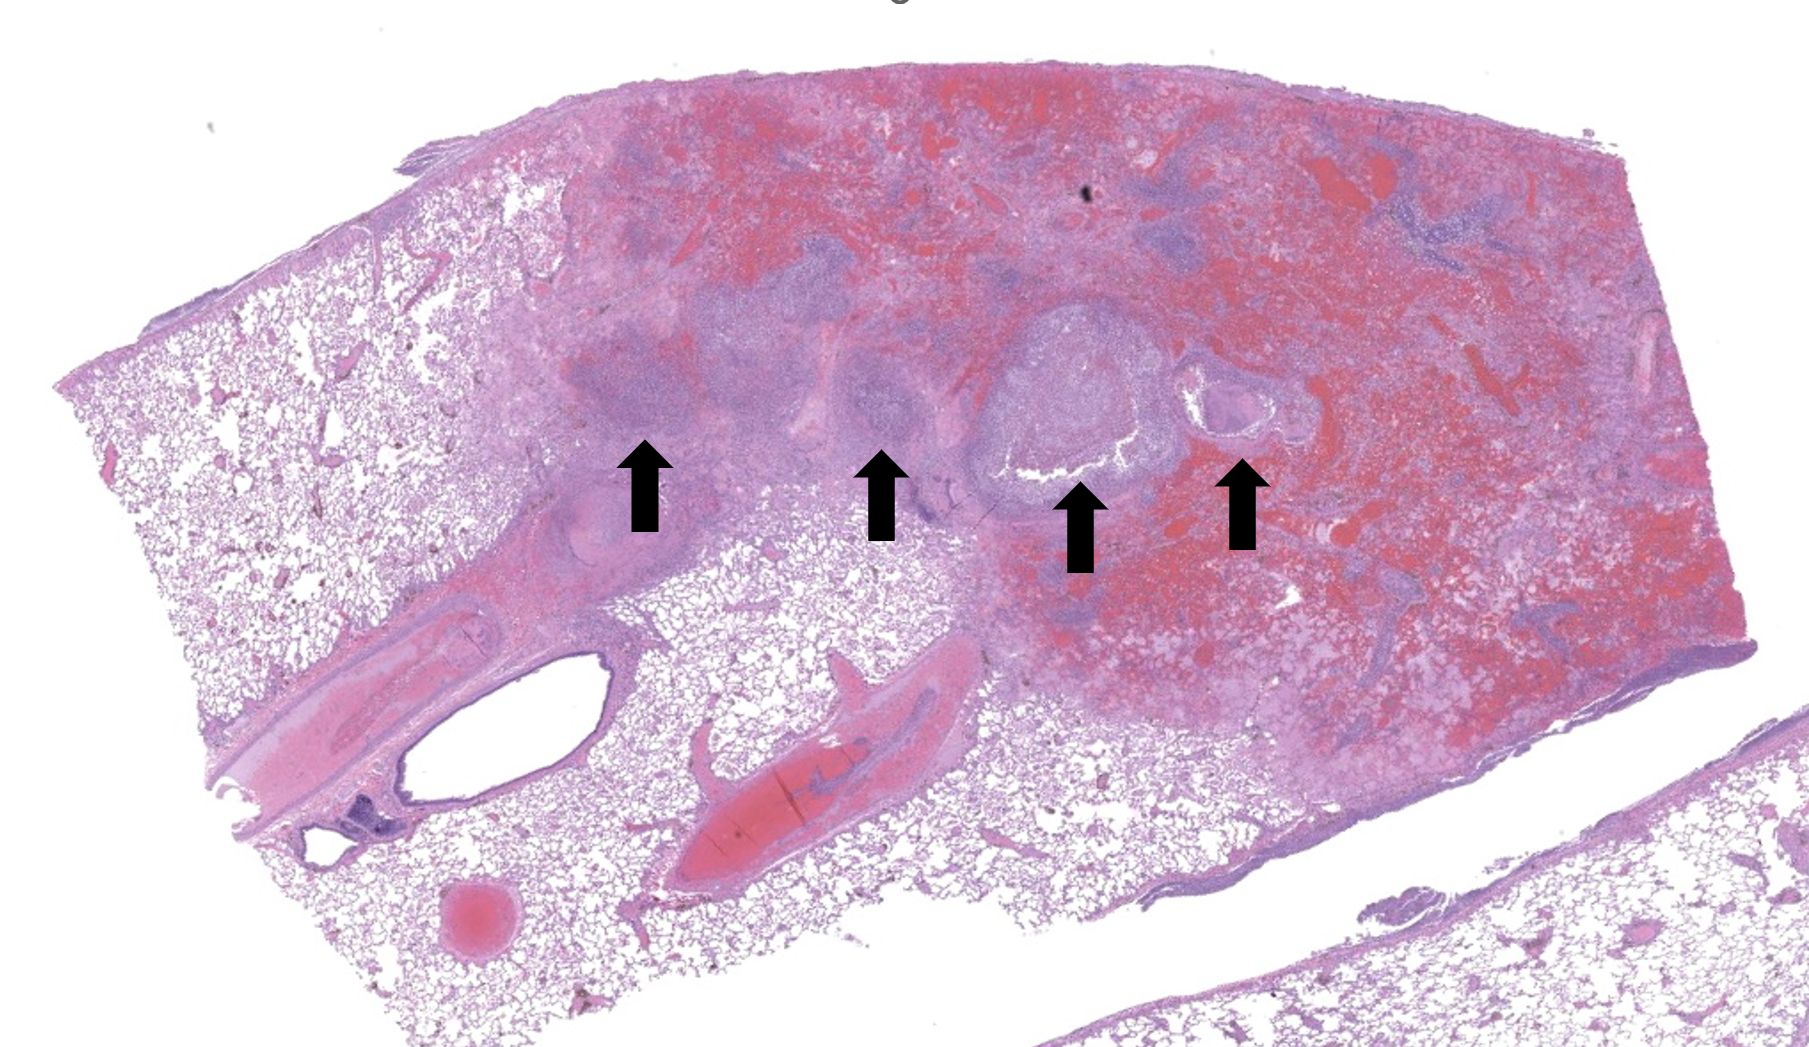

Regionally, sharply demarcated areas of the pulmonary parenchyma are markedly necrotic and replaced by abundant hemorrhage, fibrin, inflammatory infiltrates composed mainly of neutrophils and macrophages, and necrotic cellular debris. In these areas, multiple blood vessels contain thrombi consisting of large numbers of degenerate neutrophils, organizing fibrin, occasional colonies of bacterial coccobacilli, and necrotic cellular debris that variably obscure the lumen and vessel walls. Affected vessels often have smudgy, hypereosinophilic walls that are transmurally infiltrated by neutrophils, lymphocytes, and macrophages. In less affected regions, the alveolar spaces contain a small amount of fibrin, numerous foamy alveolar macrophages (some of which contain brown granular hemosiderin pigment), and fewer neutrophils and erythrocytes. There are moderate numbers of hemosiderin-laden macrophages mostly concentrated around pulmonary arteries, multifocally. Regionally, along the pleural surface there is a large amount of fibrin admixed with numerous degenerate neutrophils and necrotic cellular debris. The pleura itself is mildly thickened by fibrous connective tissue and edema and is multifocally lined by markedly reactive mesothelium, characterized by plump, rounded mesothelial cells.

Heart, right atrioventricular valve: Marked, chronic, fibrinosuppurative valvular endocarditis with intralesional bacterial colonies; Mild, multifocal, suppurative epicarditisLungs: Marked, regional, suppurative, necrotizing embolic pneumonia with vascular thrombosis and intrathrombotic bacteria; Marked, regional, fibrinosuppurative pleuritis

As the adherence of bacteria and blood components to the valve leaflets progresses, irregular, raised vegetations replace the smooth valvular surface.5 Portions of such vegetations may become detached and travel throughout the body as septic emboli.5 Emboli arising from the right side mainly affects the lungs, while emboli from the left side may dislocate and travel to distant organs, such as kidney and spleen.5

In the current case, right-sided valvular endocarditis was observed, most likely a consequence of a contaminated venous injection. Septic emboli translocated to the lungs, causing pulmonary thrombosis and infarction. Bacterial cultures of the heart and lungs revealed large numbers of E. coli and fewer Staphylococcus sp.

2. Lung: Pneumonia, embolic, necrotizing and suppurative, chronic, multifocal to coalescing, severe, with septic arterial thrombi and suppurative pleuritis.